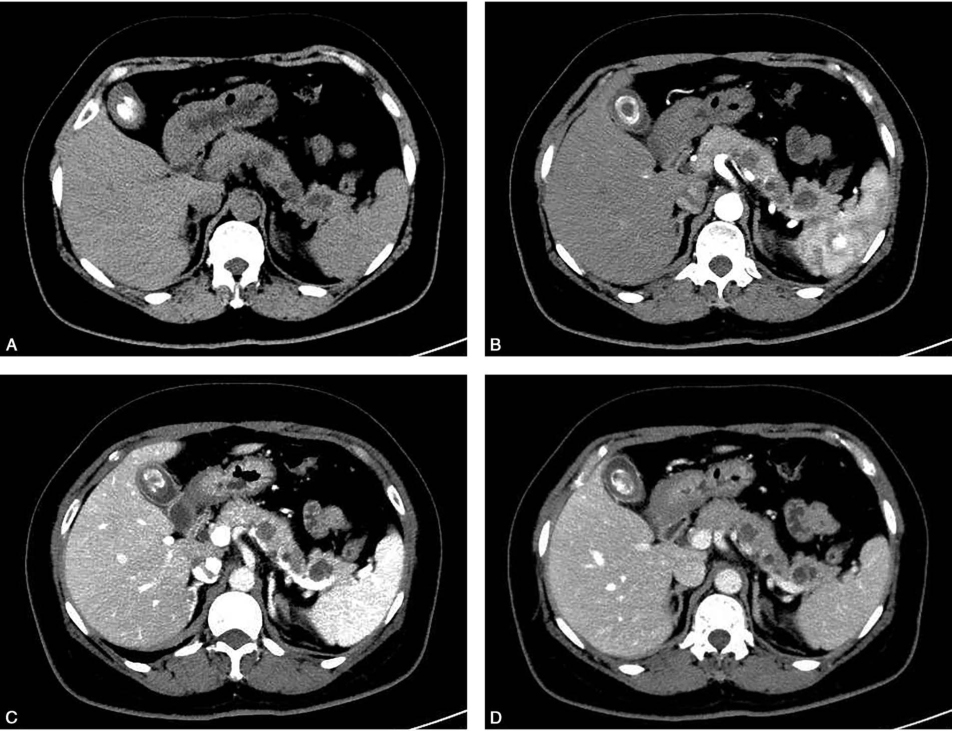

胰腺增强CT(图1)示胰体尾多发小圆形囊性低密度影,边界清晰,部分病灶内呈多房样改变,增强后分隔可见强化,胰管未见扩张。

图1 胰腺增强CT

A.平扫;B.动脉期;C.门脉期;D.平衡期。